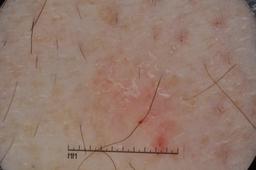

{

"age_approx": 70,

"anatom_site_general": "upper extremity",

"concomitant_biopsy": true,

"dermoscopic_type": "contact non-polarized",

"diagnosis_1": "Malignant",

"diagnosis_2": "Malignant adnexal epithelial proliferations - Follicular",

"diagnosis_3": "Basal cell carcinoma",

"diagnosis_confirm_type": "histopathology",

"image_type": "dermoscopic",

"lesion_id": "IL_9193890",

"melanocytic": false,

"sex": "male"